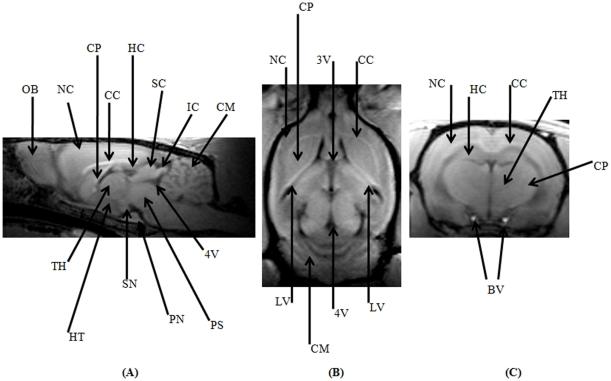

This study attempts to configure and optimize a clinical 3 Tesla magnetic resonance scanner to facilitate imaging of small animal central nervous system pathologies. The hardware of the scanner was complemented by a custom-built, 4-channel phased array coil system. Extensive modification of standard sequence protocols was carried out based on tissue relaxometric calculations. Proton density differences between the gray and white matter of the rodent spinal cord along with transverse relaxation due to magnetic susceptibility differences at the cortex and striatum of both rats and mice demonstrated statistically significant differences. The employed parallel imaging reconstruction algorithms had distinct properties dependent on the sequence type and in the presence of the contrast agent. The attempt to morphologically phenotype a normal healthy rat brain in multiple planes delineated a number of anatomical regions, and all the clinically relevant sequels following acute cerebral ischemia could be adequately characterized. Changes in blood-brain-barrier permeability following ischemia-reperfusion were also apparent at a later time. Typical characteristics of intra-cerebral haemorrhage at acute and chronic stages were also visualized up to one month. Two models of rodent spinal cord injury were adequately characterized and closely mimicked the results of histological studies. In the employed rodent animal handling system a mouse model of glioblastoma was also studied with unequivocal results.

本研究试图配置和优化临床 3 特斯拉磁共振扫描仪,以方便对小动物中枢神经系统病变进行成像。扫描仪的硬件由定制的 4 通道相控阵线圈系统补充。根据组织弛豫计算,对标准序列协议进行了广泛的修改。在大鼠和小鼠的皮质和纹状体中,由于磁化率差异导致的横向弛豫,对啮齿动物脊髓的灰质和白质之间的质子密度差异进行了广泛的测量,结果显示存在统计学上的显著差异。所采用的并行成像重建算法具有依赖于序列类型和存在对比剂的不同特性。试图在多个平面上对正常健康大鼠的大脑进行形态表型分析,描绘了许多解剖区域,并且可以充分描述所有与临床相关的急性脑缺血后的后续情况。缺血再灌注后血脑屏障通透性的变化在稍后时间也变得明显。在急性和慢性阶段的颅内出血的典型特征也可以在一个月内进行可视化。两种啮齿动物脊髓损伤模型也得到了充分的描述,并与组织学研究的结果非常相似。在采用的啮齿动物处理系统中,还对胶质母细胞瘤的小鼠模型进行了研究,结果明确。